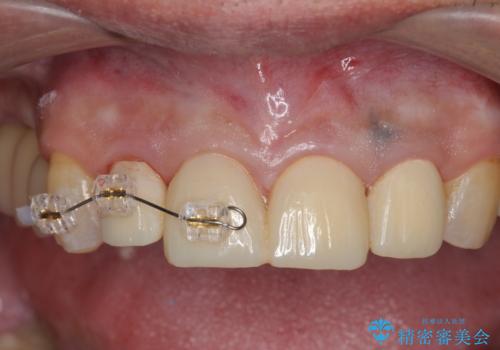

「 放置した虫歯 」 前歯セラミック治療

- 前歯の虫歯に気付きながらも放置し、一念発起し治療を希望され来院されました。

虫歯のマイクロスコープによる丁寧な除去、根管治療、深い虫歯に対する挺出(エクストリュージョン)および歯周外科を行ったのち精度の高いセラミッククラウン製作治療を計画します。

虫歯の放置により、根管治療や深い虫歯に対する処置が必要になりましたが丁寧に一つづつ処置を行ったことで抜歯をすることなく歯を残すことができました。

セラミッククラウンの製作をする前に、歯内・歯周環境の整備は非常に大切です。